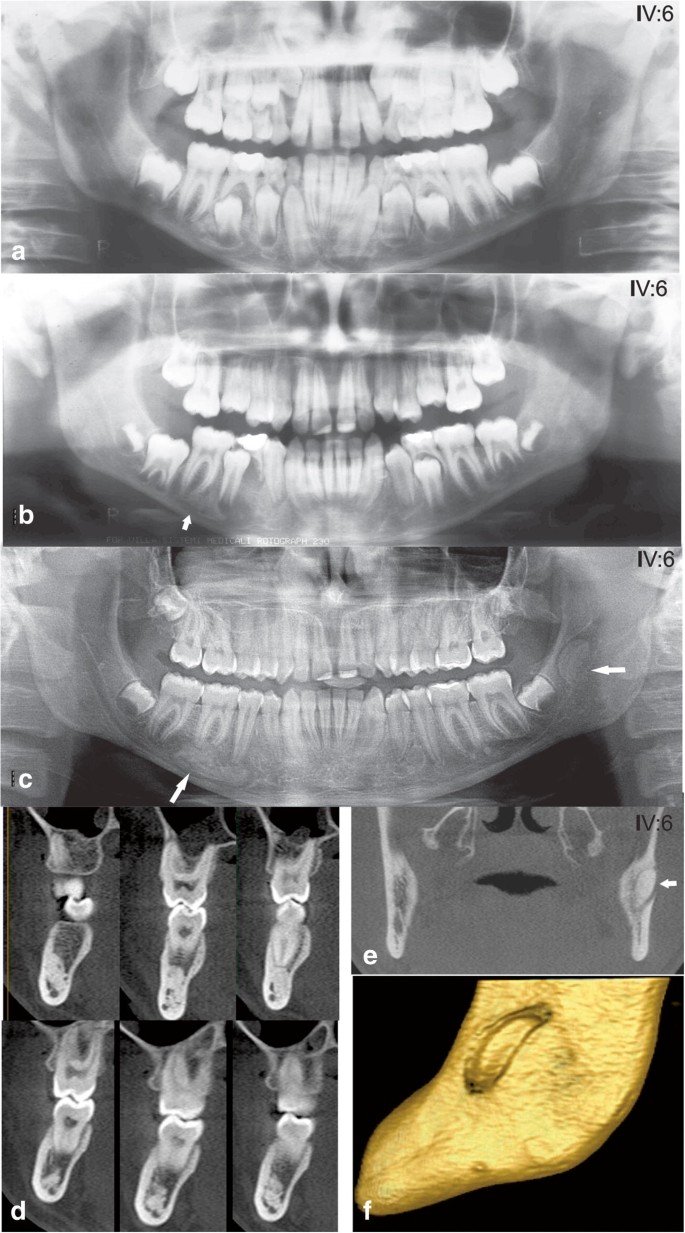

Clinical and radiological findings in Gardner's syndrome: a case report and follow-up study

image size: 2128x2800